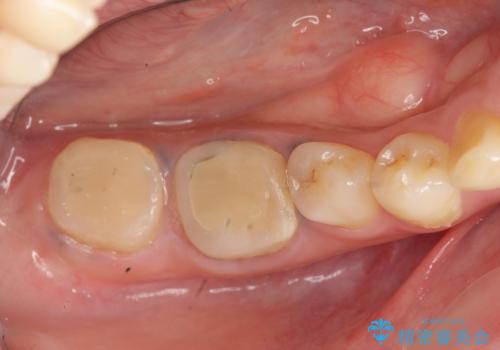

歯周外科を行うことで、歯ぐきの位置を下げ歯の高さを作り出し安定したクラウンの装着が可能となります。また同時に舌の邪魔となっていた骨隆起の除去を行うこととしました。

- 37.4万円(ジルコニアクラウン×2・仮歯×2・歯周外科手術)費用は治療当時の料金となります